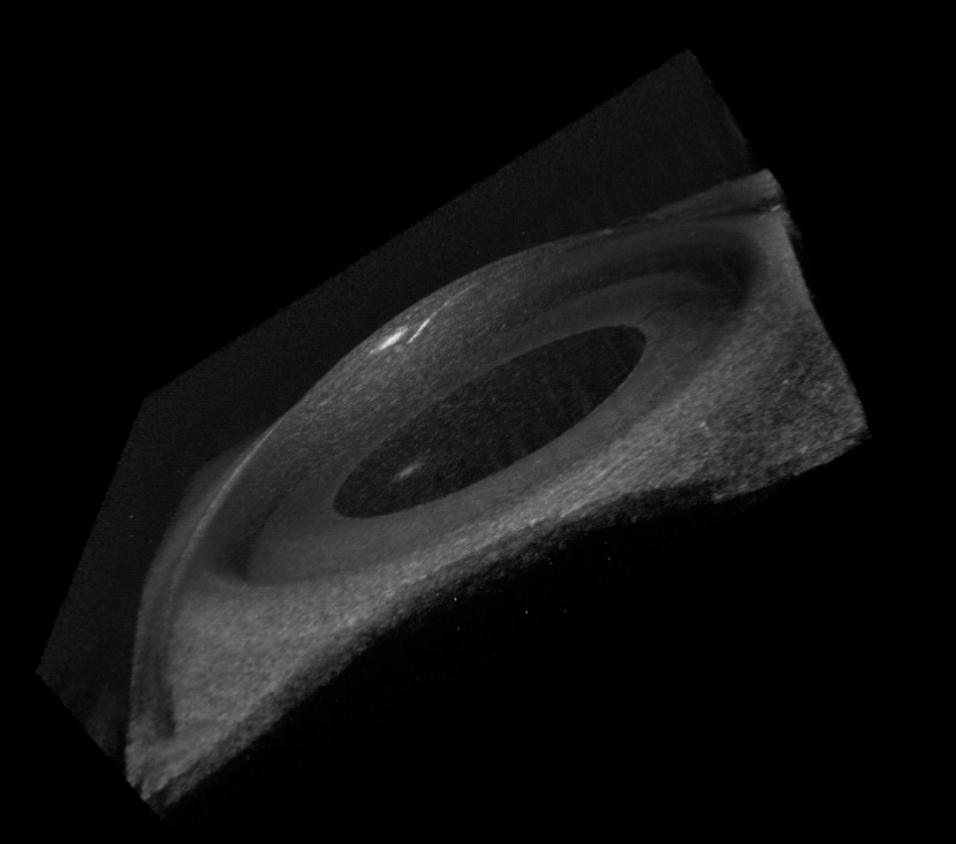

Multi-functional optical coherence tomography (OCT) system for corneal assessment

Optical coherence tomography (OCT) is a non-invasive, non-contact imaging technology which is developed to obtain tissue cross-section image with high resolution. PolyU’s research team has successfully developed a cutting edge technology to combine a novel air-jet method and OCT for assessing the mechanical properties of cornea. This newly invented technology can measure corneal parameters like corneal thickness, optical index, and biomechanical parameters in a non-contact way. It has great potential for corneal assessment in ophthalmology and optometry.